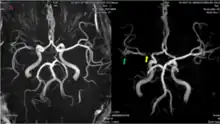

The leptomeningeal collateral circulation (also known as leptomeningeal anastomoses or pial collaterals) is a network of small blood vessels in the brain that connects branches of the middle, anterior and posterior cerebral arteries (MCA, ACA, and PCA),[1] with variation in its precise anatomy between individuals.[2] During a stroke, leptomeningeal collateral vessels allow limited blood flow when other, larger blood vessels provide inadequate blood supply to a part of the brain.[3]

Leptomeningeal collaterals lie within the leptomeninges, the two deep layers of the meninges called the pia mater and the arachnoid mater.[4] Their diameter has been measured at approximately 300 micrometers,[5] but there is variability between individuals in the size, quantity and location of these vessels, and between either hemisphere within the same subject.[6]

Inter-territorial end to end anastomoses exist between branches of the anterior cerebral artery and middle cerebral artery, the posterior cerebral artery and middle cerebral artery, the anterior cerebral artery and posterior cerebral artery, and the right and left anterior cerebral arteries.[7][8][9][10] Intra-territorial anastamoses connect adjacent arterial branches within the same arterial territory (between two branches of the same middle cerebral artery, for example).[5]